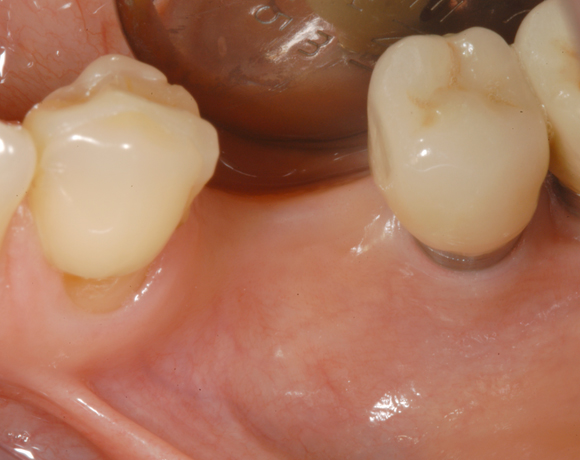

Knochenspaltung Unterkiefer 45 – 47

Im vorliegenden Fall war zwar eine gut Knochenhöhe vorhanden, jedoch war der Knochen zu schmal,